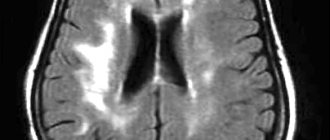

Sonologists use modern ultrasound machines that combine a triplex scanner and a Doppler unit. They make it possible to visualize the extracranial and intracranial sections of the arteries of the vertebral-basilar region and identify the asymmetry of blood flow in the MCA and ACA. To determine the state of neurons during cerebral ischemia, magnetic resonance and computed tomography are performed using premium devices. CT angiography of cerebral vessels at the Yusupov Hospital is performed on a modern scanner. Using it, not only step-by-step images of cerebral vessels are obtained, but also their three-dimensional model. These images can be viewed on a computer monitor, printed on film, or transferred to a DVD+R disc.

Signs of vasospasm in the left arteries of the brain, MCA and ACA often occur in those patients in whom early magnetic resonance or computed tomography of the brain showed layers of coagulated blood 1 mm thick or more in the sulci of the brain or spherical blood clots larger than 5 mm3 in the basal cisterns.

Doctors at the Yusupov Hospital determine the localization and severity of vasospasm in the ACA and MCA using magnetic resonance or computed tomography. To ensure an accurate prognosis, a CT scan of the brain is performed between 24 and 96 hours after subarachnoid hemorrhage.

If the entire brain area in the MCA basin (middle cerebral artery) is subject to ischemia or infarction, its edema develops, which can lead to increased intracranial pressure. Early magnetic resonance or computed tomography of the brain can predict an unfavorable outcome if a large blood clot is detected in the Sylvian cistern or in the lumen of the Sylvian fissure and a second significant clot in the basal frontal fissure, located between the cerebral hemispheres. The simultaneous presence of clotted blood in these areas is combined with severe symptomatic spasm of the MCA and ACA. In such a situation, superficial collaterals in the cerebral cortex from the ACA are not able to compensate for ischemia in the MCA territory.